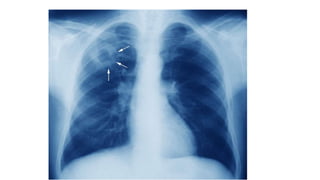

4. Chest X-ray and other relevant radiological investigations

• Chest X ray

• CT – chest (High resolution CT)